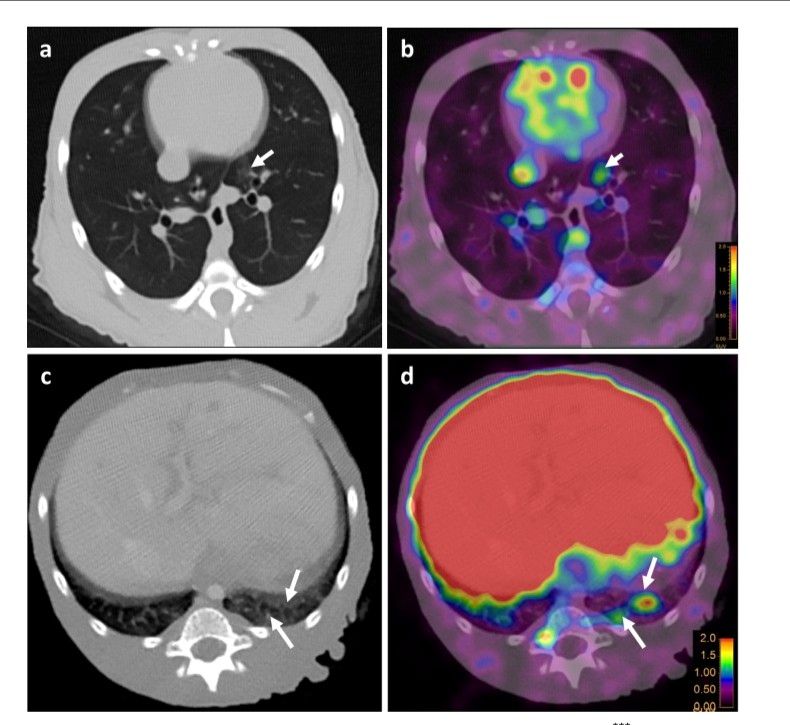

SARS-COV-2 Invades Lungs, Brain, Nasal Passages, Airways, and Kidneys: Imaging Tracks COVID-19's Hidden Locations 3 months after infection https://t.co/vfuxc952wY